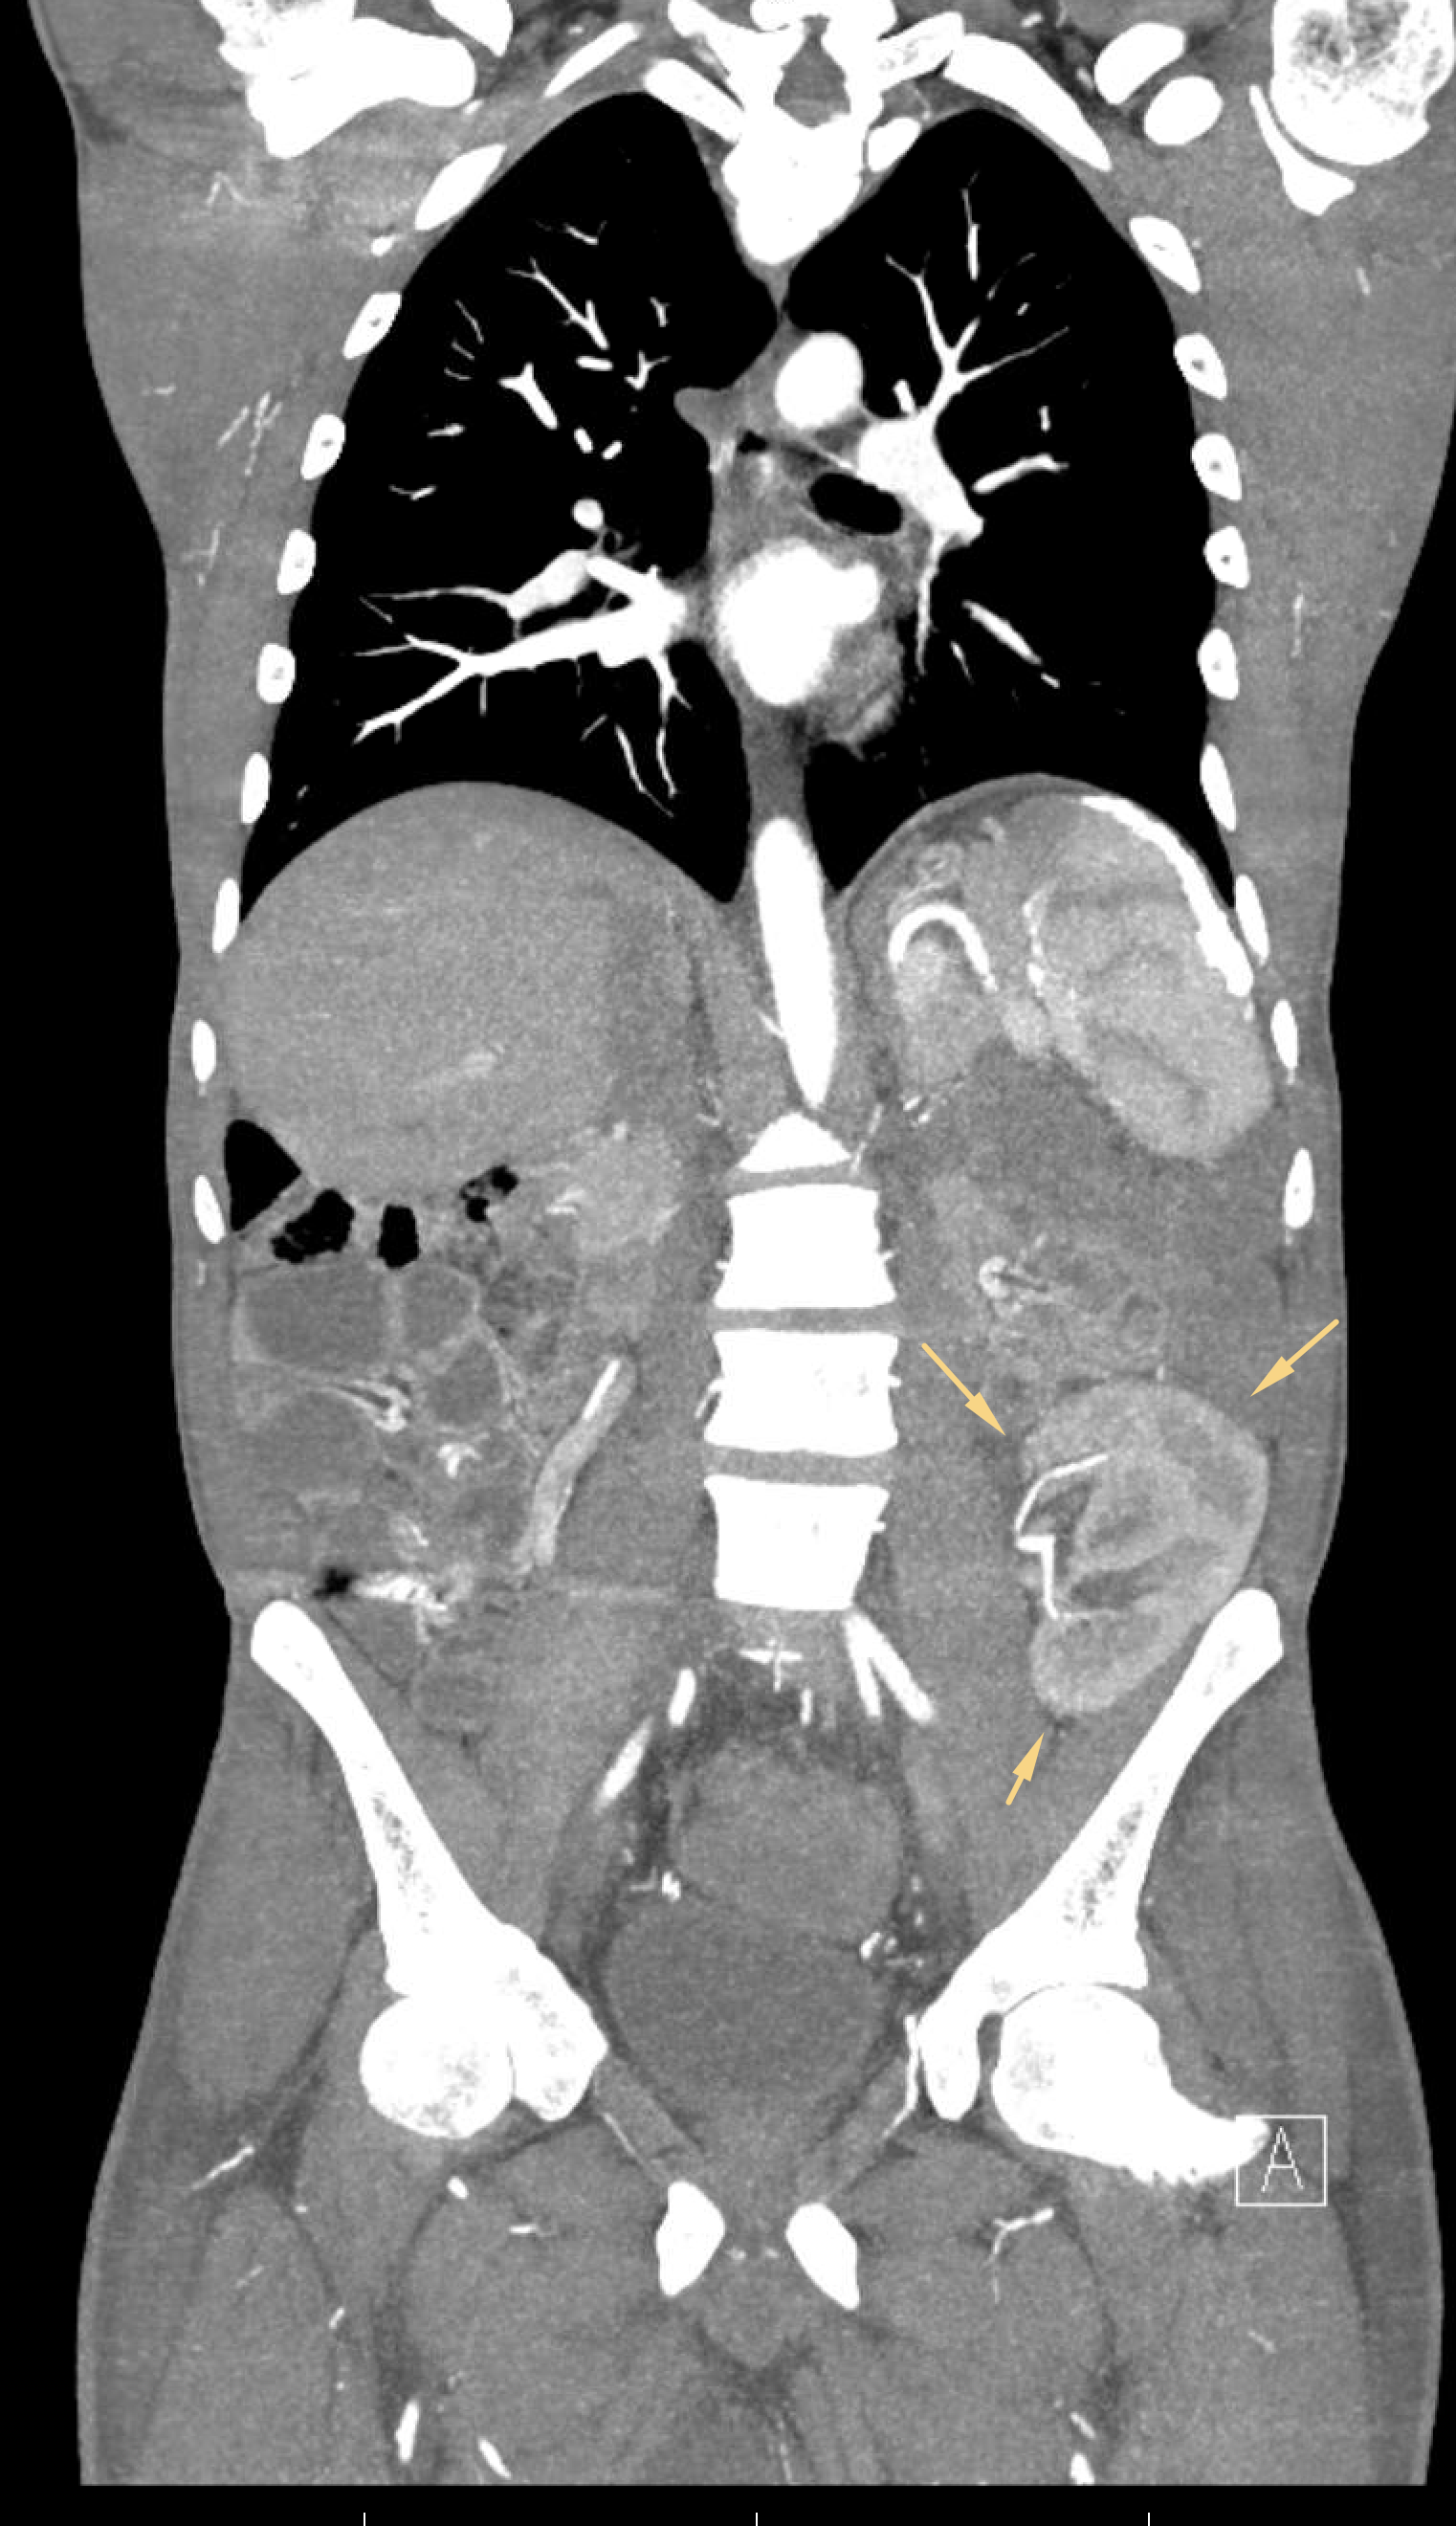

Age: 37

Sex: Male

Indication: Anemia

Radiotracer: Tc99m Labeled RBCs

Sample ReportNo evidence of the active GI bleeding during the course of this study.